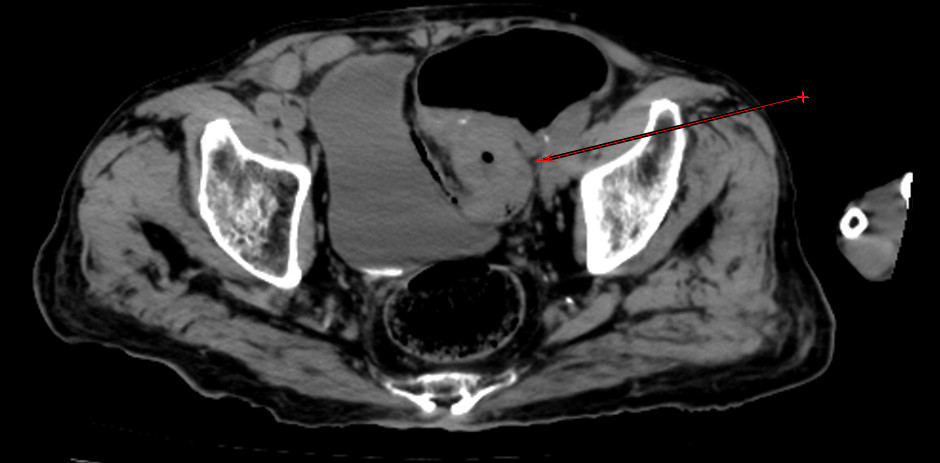

"患者意识不清,双侧瞳孔不等大!"接诊医生周淑清的呼喊打破了夜的宁静。急诊团队立即启动绿色通道,15分钟内完成头胸腹CT检查。

结果令人揪心:急性脑出血合并乙状结肠癌完全性肠梗阻,肠镜结果乙状结肠肠腔完全堵死。"就像两把刀同时架在脖子上。"患者的主治医师邵庆亮这样形容当时的危急情况。